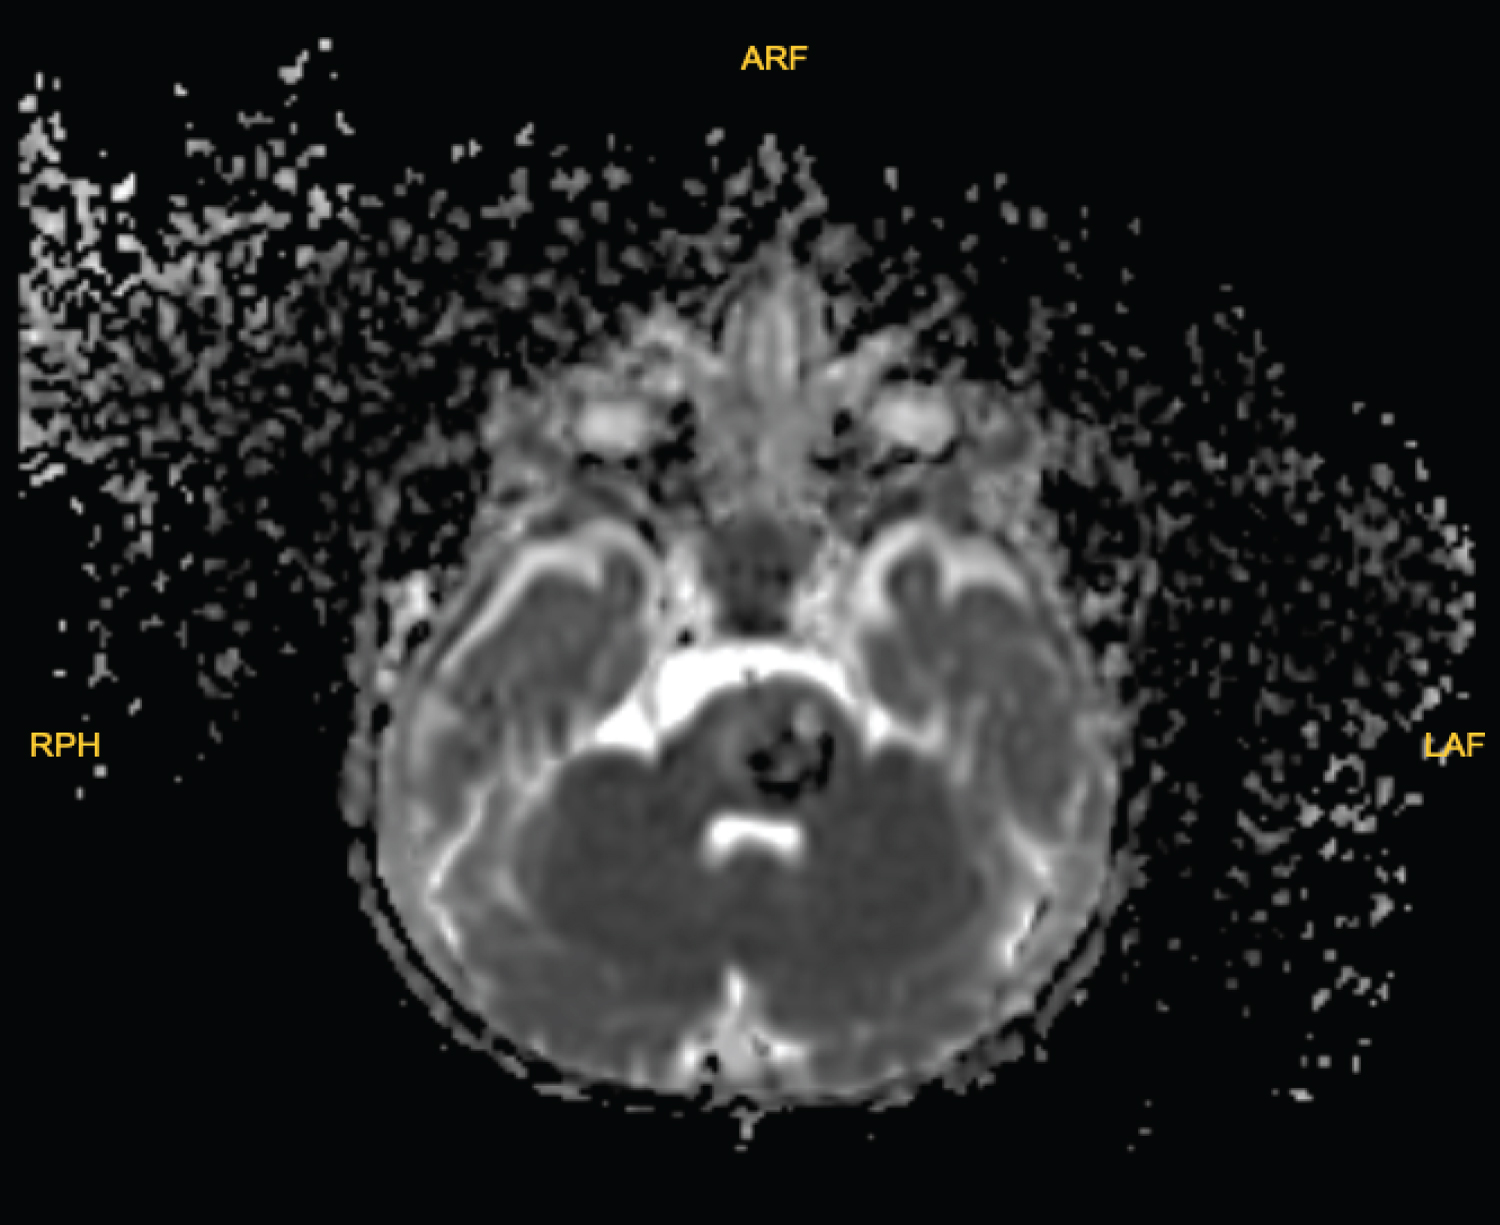

He was required hospitalization with focal neurologic deficit and admitted to pediatric ICU service to complete preoperative studies. After 12 hours of admission, our team was ready for surgery but on the operation table he has fever of 38.5 °C anesthesia wanted to exclude COVID-19 infection and sent him back to ICU. Blood cultures and urine cultures were made and nasopharyngeal swab culture for COVID-19 was sent to the public health laboratory of Turkish Health Ministry. Prophylactic antibiotics were started. Tests were revealed after 2 days and showed no infection and his fever was improved. 2 days later we operated patient. A suboccipital craniectomy was performed. The lesion appeared vascular and clearly separated from the normal glial tissue without involvement. Because of the patient's size and the low circulating blood volume, minimizing blood loss was imperative. Blood products were on standby but neither of was used. Hemangioma was gross totally resected and no complication was made. After surgery to exclude intracranial hemorrhage, a diffusion MRI was obtained and revealed the lesion was totally resected. No hemorrhage was seen (Figure 3 and Figure 4). On his post-operative day 1, his hemiparesis was 4+/5 but had a facial paresis so we immediately started 2 mg/kg/h prednisolone and continued for 24 hours. In his post-operative day 2, his facial paralysis was recovered and we stopped prednisolone infusion. He was transferred to infantile service, near his parents. We checked his neurologic examination on our daily routines and his right paresis was totally improved on post-operative day 5 and he discharged with outpatient polyclinic control.

Figure 3: Postoperative 24 hour MRI, no hemorrhage was seen on the MRI. View Figure 3

Figure 4: Postoperative Day 30 control MRI, lesion was totally removed. T1, TOF and T2 flair sequences of MRI images. View Figure 4

On his post-operative day 12 we took sutures and no cerebral spinal fluid collection was seen. We planned a control magnetic resonance angiography and obtained in his post-operative day 30 (Figure 4). No residue lesion was revealed.